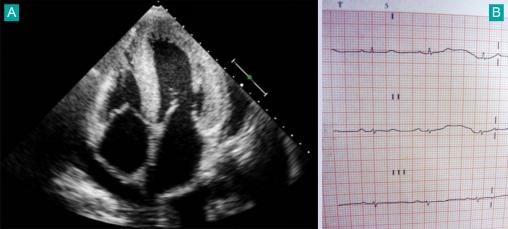

Amylose cardiaque, échographie (A) et ECG (B)

Association cardiopathie hypertrophique et microvoltage très évocatrice du diagnostic.